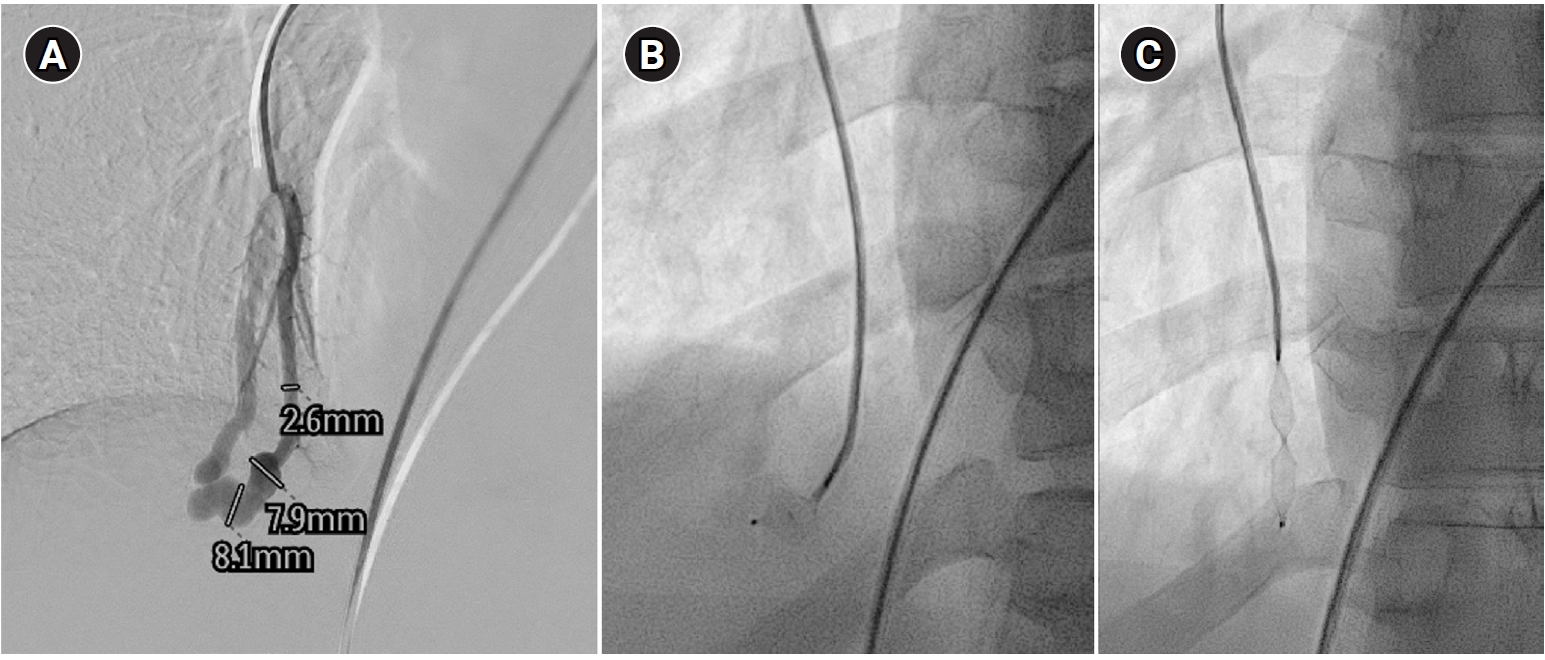

Fig. 1.

Agitated saline bubble echocardiography images. (A) After injection of agitated saline bubbles into a peripheral vein, echogenic bubbles are seen filling the right heart. Under normal conditions, the bubbles are completely filtered by the pulmonary capillary bed, and no bubbles appear in the left cardiac chambers. (B) After the appearance of bubbles in the right cardiac chambers, bubbles are subsequently observed in the left cardiac chambers after three cardiac cycles, indicating the presence of an extracardiac shunt (pulmonary arteriovenous malformation). RA, right atrium; RV, right ventricle; LA, left atrium; LV, left ventricle.

HHT is an autosomal dominant disease with an estimated prevalence of 1 in 5,000 [7]. It is characterized by clinically significant vascular lesions involving the skin and mucosa (nasal and gastrointestinal), as well as the brain, lungs, and liver. It is underdiagnosed, and a long diagnostic delay is common [8]. A diagnosis of HHT allows appropriate screening and preventive treatment to be undertaken in a patient and their affected family members. The most common symptom of HHT, epistaxis, has an age-related expression, as does the appearance of the typical telangiectasia (Fig. 1). The diagnosis of HHT is well described in Curaçao criteria (Table 1). In patients with symptoms or signs of a PAVM by history and/or physical examination, contrast-enhanced or agitated saline bubble echocardiography remains the best initial screening tool because of its high sensitivity and negative predictive value approaching 100% (Fig. 1) [9]. According to the expert panel, if HHT is confirmed or suspected, a workup for PAVMs is necessary, and for this workup, contrast-enhanced echocardiography is recommended [10].

Fig. 1. Agitated saline bubble echocardiography images. (A) After injection of agitated saline bubbles into a peripheral vein, echogenic bubbles are seen filling the right heart. Under normal conditions, the bubbles are completely filtered by the pulmonary capillary bed, and no bubbles appear in the left cardiac chambers. (B) After the appearance of bubbles in the right cardiac chambers, bubbles are subsequently observed in the left cardiac chambers after three cardiac cycles, indicating the presence of an extracardiac shunt (pulmonary arteriovenous malformation). RA, right atrium; RV, right ventricle; LA, left atrium; LV, left ventricle.